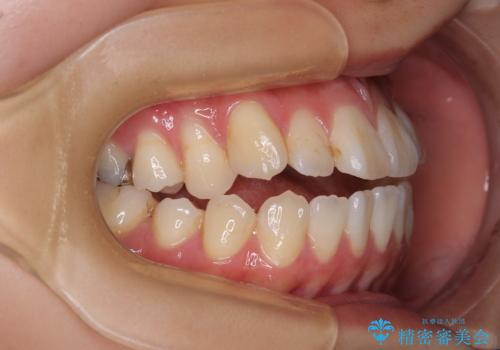

舌の突出癖が原因 インビザライン矯正による開咬改善

- 前歯の開咬を気にして来院された患者様です。

開咬の治療は、前歯を閉じるように動かすとともに、上下臼歯を圧下(骨内にめり込ませる)させることで進めて行きます。

インビザラインは臼歯の圧下を効果的に行えるため、インビザラインを用いて矯正治療を行うこととしました。

オープンバイトは舌の突出癖により誘発され、治療後も突出癖が残っている容易に後戻りしてしまいます。

治療期間を短縮するためにも、舌突出癖の改善が極めて重要となります。